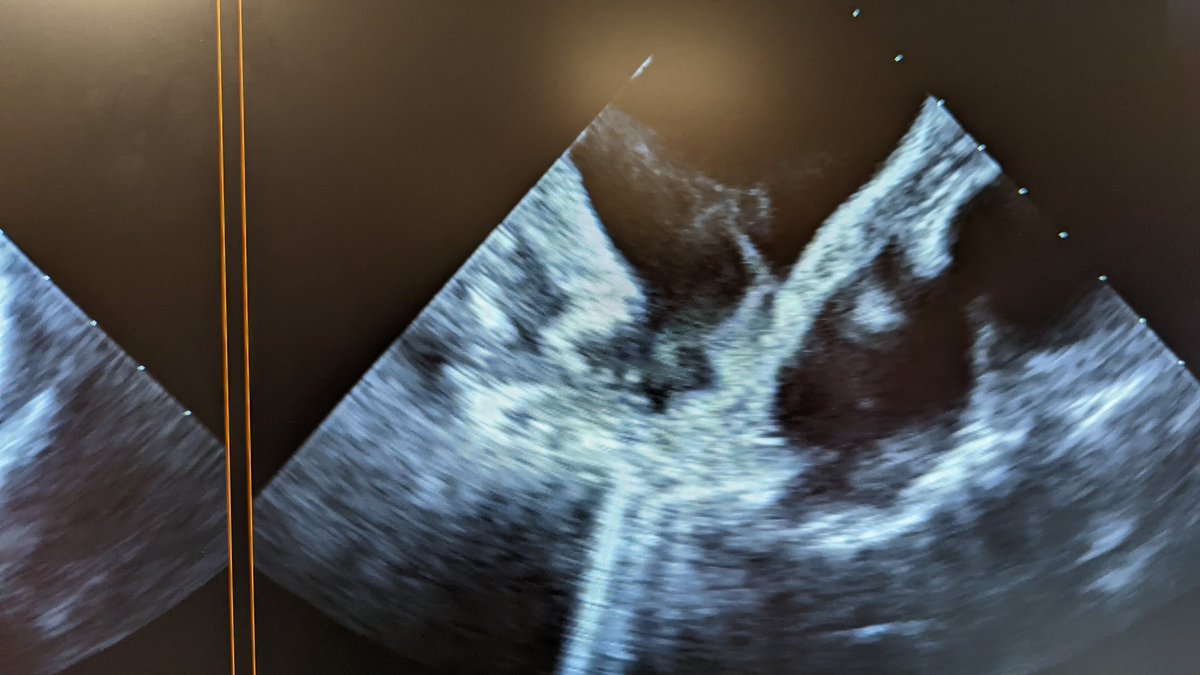

LAA almost completely occluded by clot. 85 yo patient off OAC because of a history of fall that caused large subdural hematoma. #EPeeps

LAA almost completely occluded by clot.

85 yo patient off OAC because of a history of fall that caused large subdural hematoma.

#EPeeps